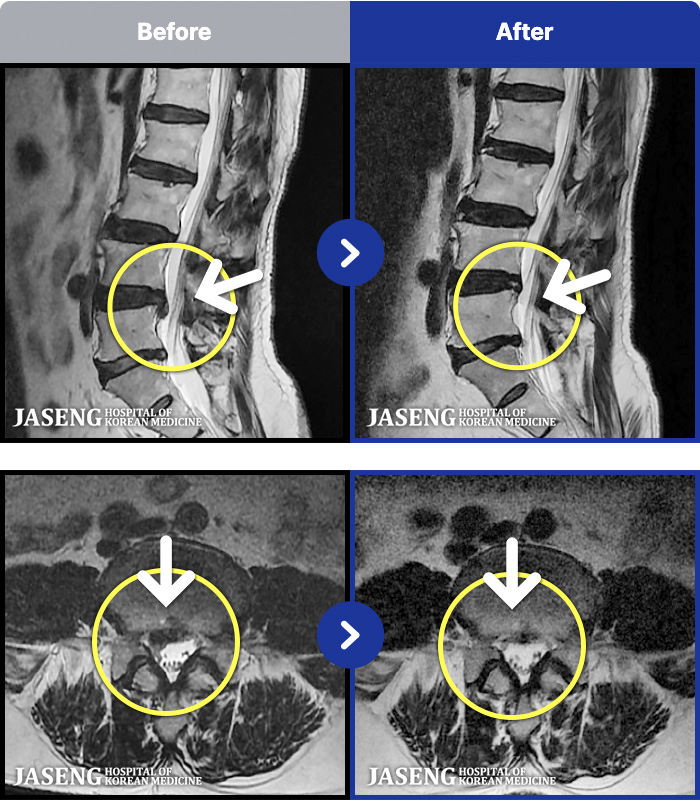

[뱸] 19.11.28~25.05.06